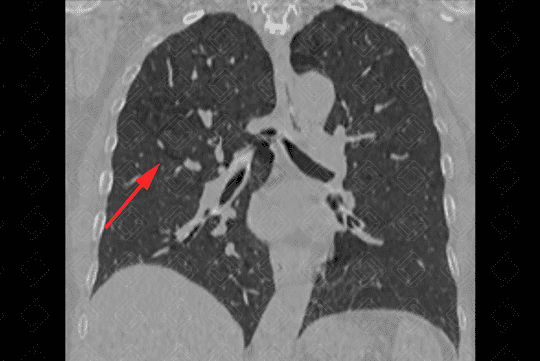

Descrição das figuras 3, 4, 5 e 6: Tomografia computadorizada do tórax seguida de aquisições coronais, sagitais e axiais mostrando as extensas áreas de enfisema centrolobular dispersas pelo parênquima pulmonar (setas vermelhas).

• Tomografia computadorizada do tórax: Este método é mais sensível e específico que a radiografia de tórax na avaliação do enfisema. Tem sido empregado para detectar, quantificar e caracterizar a doença. A tomografia é capaz de diferenciar os vários tipos de enfisema, que pode ser classificado, de acordo com a região do ácino acometida, em proximal (centrolobular ou centroacinar - figuras 3, 4, 5, 6, 9, 10 e 11 ), distal (parasseptal - figuras 7, 8, 9, 10 e 11 ) ou todo ácino (panacinar ou panlobular).